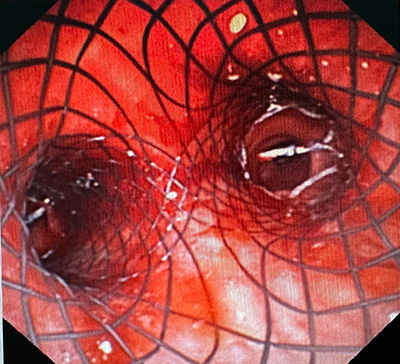

最终团队于气管镜直视下置入Y形金属覆膜支架,支架位置精准、释放完全。整个手术操作规范、流程顺畅,全程仅耗时半小时即顺利完成。“血氧饱和度上来了!95%、98%……稳定了!”术后即刻,手术室里传来振奋的通报声,W先生喘息症状显著缓解,呼吸困难改善,生命体征平稳,片刻转危为安。

Y形金属覆膜支架置入后